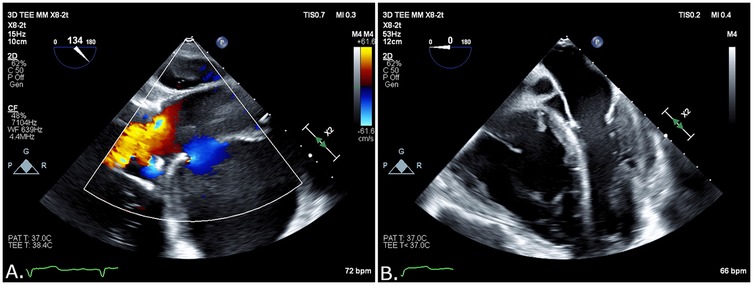

At 9 months after initial surgery, the patient became symptomatic and developed dysphagia and shortness of breath and was admitted to the same referring hospital. At this time, his TTE demonstrated moderate reduction in left ventricular systolic function with a suspected pseudoaneurysm of the ascending aorta (Figure 1A). Computed tomography angiography (CTA) confirmed the diagnosis with an anterior ascending aortic pseudoaneurysm measuring 11.5 cm over 8.5 cm, originating 2 cm above the RCA ostium (Figure 1B). The CTA also indicated that only the LIMA to the LAD graft was patent, while both SVG grafts and the native RCA were occluded.

Figure 1

Panel A shows an ultrasound of the heart indicating a pseudoaneurysm. Structures labeled include RVOT, LVOT, LV, LA, and Asc Ao. Panel B is a CT scan displaying the heart in a cross-sectional view with an asterisk marking a specific area likely indicating the pseudoaneurysm.

Figure 1. (A) Echocardiography. PLAX view with a decrease in left ventricular function and suspected pseudoaneurysm of the ascending aorta. (B) CTA scan with an anterior ascending aorta pseudoaneurysm showing a mass effect on the heart and pulmonary arteries. CTA, computed tomography angiography; PLAX, parasternal long-axis.